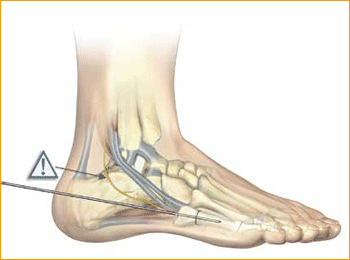

Calcaneal Osteotomy Technique for 6.5 mm Headless Compression screws.

1. PATIENT POSITIONING

Position the patient at the end of the bed, semi-lateral. Check that the leg can be placed easily onto the mini c-arm prior to preparation of the operative limb.

2. APPROACH AND EXPOSURE

An incision is made posterior to the peroneal tendons, perpendicular to the body of the calcaneus. Cephalad and caudal mini Hohman Retractors are

placed to protect the neurovascular structures and plantar fascia. Care is made to preserve the peroneal tendons and the sural nerve.

3. CREATE OSTEOTOMY

An oscillating saw is used to make the osteotomy cut perpendicular to the body of the calcaneus. The saw is not used to complete the cut through the medial cortex. This is completed with an osteotome in order to avoid damaging medial neurovascular structures.

4. GUIDE WIRE PLACEMENT

The body of the calcaneus is displaced medially or laterally and held in place with two guide pins. The distal portion of the pins are placed at the volar aspect of the angle of Gissane in order to capture solid bone distally and assist with compression of the osteotomy by the screws.

Confirm guide pin placement under fluoroscopy.

Tip: The soft tissue protector and arthroscopic probe can be used to assist in guide wire placement.

5. MEASURE DEPTH

Select a screw the same size as measured. However, to account for countersinking and compression it is common to select a screw one size shorter

than the measured depth. After selecting the size, advance the guide wire approximately 5 mm to maintain distal pin fixation before drilling.

Caution: Make sure not to compromise joint surfaces when advancing the guide wire.

6. SELECT SCREW SIZE

Place the soft tissue guide (the guide should be used throughout) over the guide wire and open the near cortex using the appropriate cannulated profile drill.

7. SOFT TISSUE GUIDE

Place the soft tissue guide over the guide wire and open the near cortex using the appropriate cannulated profile drill.

Tip: Drills should be advanced slowly with continuous irrigation to minimize the potential of heat build-up. Clean drill periodically during each procedure to optimize performance.

8. DRILL

Leaving the soft tissue guide in place, drill into the far fragment with the appropriate cannulated, long profile drill. Reference the markings on the drill to confirm desired depth.

Tip: The long drill is recommended to mitigate the effects of varying bone density and distraction upon screw insertion.

9. SCREW INSERTION

Cannulated Screws are placed. Placement is confirmed by lateral and axial fluoroscopy views in the operating room.

Caution: The marking on the driver shows when the screw is approximately flush with the end of the soft tissue protector; assure that the soft tissue protector is touching bone to accurately determine screw depth. Verify final screw position with fluoroscopy.

10. ADDITIONAL SCREW PLACEMENT

Repeat steps 5–9 for each additional screw placement. The operative limb is placed into a bulky compression dressing. A splint is also placed. Patients are made non-weight-bearing in a cast, boot, or splint for 6 weeks after surgery.